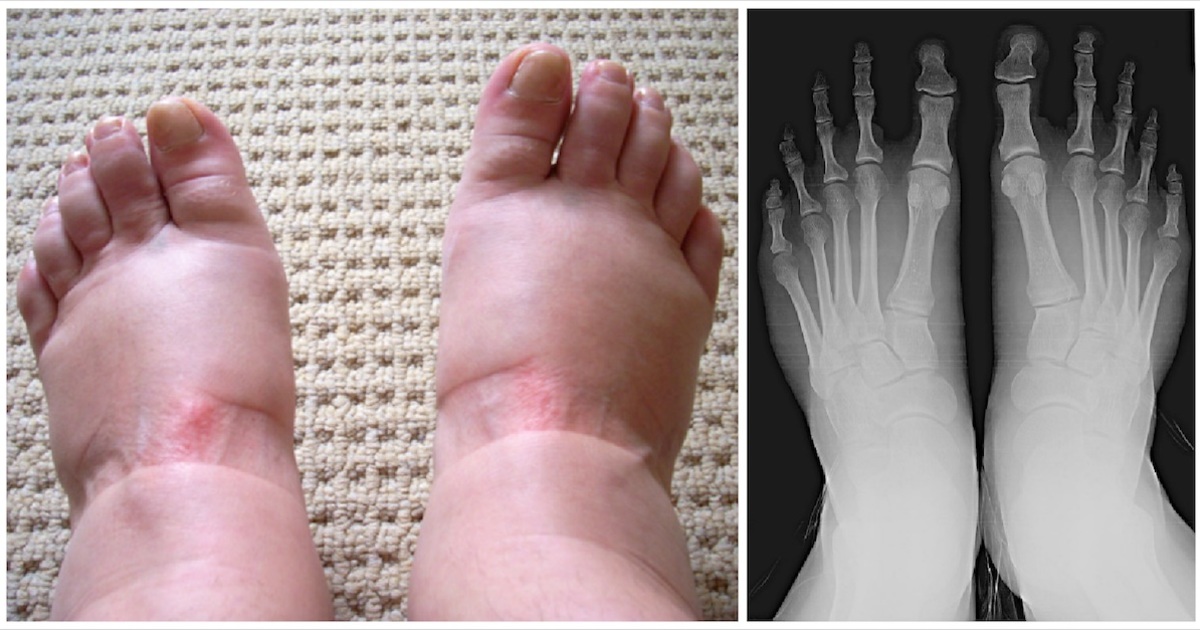

Cause #7: Gout

One of the most painful forms of arthritis, gout occurs when too much uric acid accumulates in the body, writes the National Institute of Arthritis.

Gout usually comes suddenly and often starts at night. Often, the inner joints of the big toe quickly become tender, red, and swollen.

If you have severe pain or if it’s the first time you’ve experienced this, seek medical advice immediately.